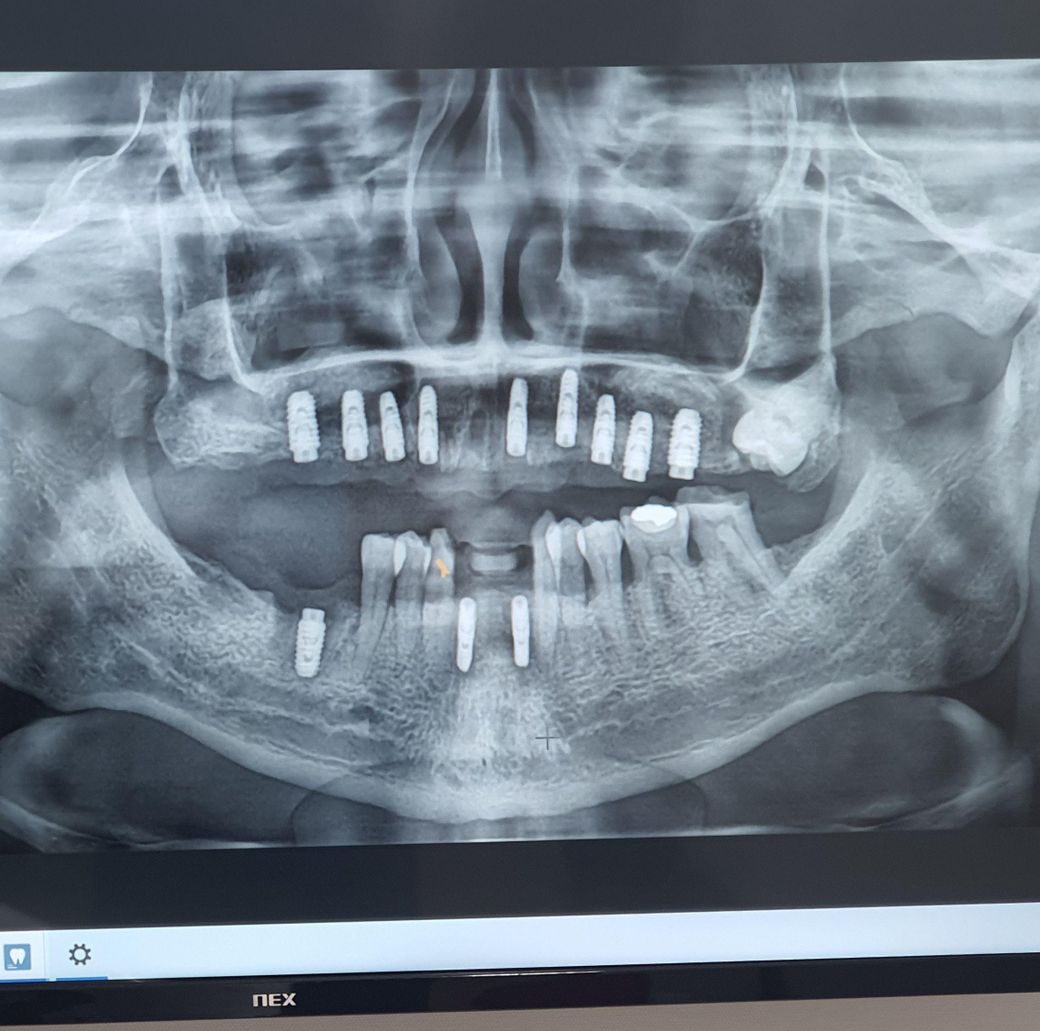

임플란트 하악쪽에 염증있네요 함 봐주세요

하악밑에니 임플란트 나사 식릭한지 오늘 딱 42일째입니다. 밑에니 이빨뽑고 임플란트 식립하기전에도 종종 잇몸에 염증이 생겨서 몇번터트린적 있었는대..병원에서 ct등 다찍고 했는대 이런거 확인안하고 심었을까요..

서울강남 서울대출신의사들 많아서 믿고했는대 정말허탈합니다. 10월 1일날 일주일전에 상악쪽 실밥풀러가면서 분명히 하악쪽아랫니 통증있다고해서 파노라마찍고 했는대 아무이상없다더니 염증있네요. 염증이 겉으로 안보여서 몰랐는대 오늘잇몸보니 하악아랫니가 염증차있습니다. 이거 나사 다시빼야하나요? 그리고 1년무상 AS니까 공짜로 다시해주겠죠?

엑스레이 상으로는 염증이 있어 보이진 않습니다 그리고 만약 문제가 생긴다면 a/s를 다시 해줄테니 너무 걱정하지마세요.